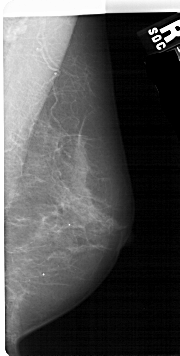

A_1686_1.LEFT_MLO

LEFT_MLO LINES 5491 PIXELS_PER_LINE 2701 BITS_PER_PIXEL 12 RESOLUTION 43.5 OVERLAY

FILE: A_1686_1.LEFT_MLO.OVERLAY

TOTAL_ABNORMALITIES 1

ABNORMALITY 1

LESION_TYPE MASS SHAPE IRREGULAR MARGINS ILL_DEFINED

ASSESSMENT 4

SUBTLETY 3

PATHOLOGY BENIGN

TOTAL_OUTLINES 1

BOUNDARY